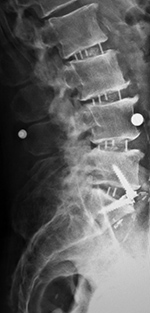

| Pedicle fixation screws and rods |

| 20 year-old woman with L1 vertebral body compression fracture treated with T12-L2 posterior spinal fusion using pedicle screws at T12 and L2 with connecting rods on each side. |